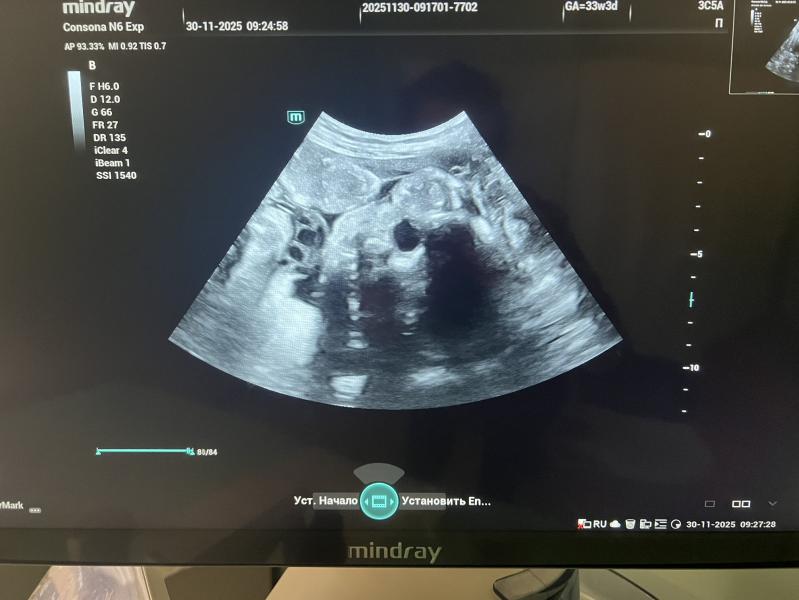

Нам 33 недели и 4 дня

На узи не особо поняла-тритий скрининг.

Лёг так, что я вообще не понимаю где и что, но рукой помохал-это хорошо.

Вес-1833, рост 43, а ножка уже-6см.

Я вот в этот раз вообще не смогла его поймать) врач то понимает, а я все пытаюсь что то углядеть-а он танцы устраивал)